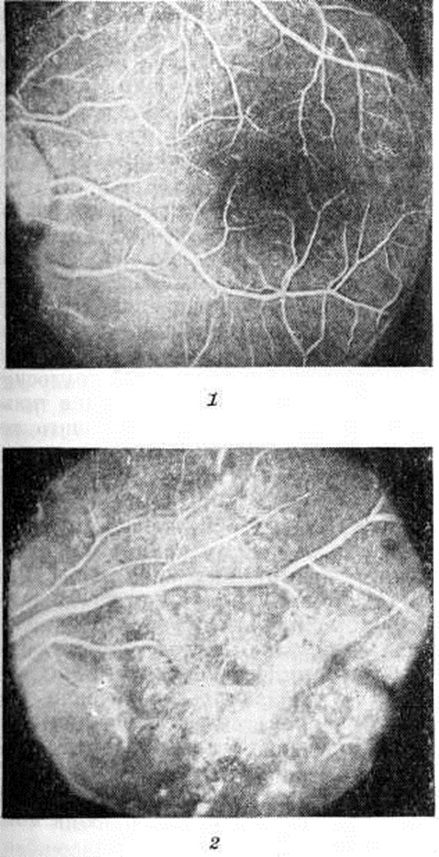

Макроскопические изменения поджелудочной железы неспецифичны. Уменьшение объёма и веса органа, липоматоз и цирроз (так называемый гранулярная атрофия) сами по себе не являются доказательством наличия Диабет сахарный, не связаны с прогрессированием заболевания. Изменения, развивающиеся при воспалении, травмах, нарушениях кровообращения, опухолях поджелудочной железы, могут приводить к вторичной инсулинной недостаточности. Для Диабет сахарный с первичной инсулинной недостаточностью морфологически критерием является нарушение соотношения между аи Р-клетками островков, которые отражают морфологически и функциональный дезорганизацию в системе глюкагон — инсулин, являющуюся основой относительной или абсолютной инсулинной недостаточности. Соотношение α-клеток и β-клеток, составляющее у здоровых людей от 1:3 до 1:5, может изменяться до 1 : 2 или 1:1. Изменение этого индекса может быть связано с уменьшением количества β-клеток (на 7— 10%), что особенно четко выявляется при юношеском Диабет сахарный При этом в сохранившихся β-клетках обнаруживаются признаки гиперплазии и гиперфункции (увеличение митохондрий, просветление матрикса, набухание эргастоплазматического ретикулума, увеличение количества секретируемого инсулина). Одновременно в таких клетках нередко отмечаются признаки альтерации. При юношеском Диабет сахарный часто возникает инфильтрация островков макрофагами и лимфоцитами, приводящая к постепенной гибели β-клеток. Аналогичные изменения наблюдаются в эксперименте при введении животным инсулина. Другая форма дезорганизации островкового аппарата — увеличение количества α-клеток при неизменённом количестве β-клеток. В ответ на это развивается компенсаторная гипертрофия β-клеток, которая также заканчивается функциональным истощением. Гистохимические исследования выявляют уменьшение содержания или исчезновение цинка из цитоплазмы β-клеток. Относительная или абсолютная недостаточность β-клеток свойственна детской, юношеской и взрослой формам Диабет сахарный, нарастает по мере длительности заболевания, обнаруживая прямую зависимость от его тяжести. Для Диабет сахарный характерно накопление гликогена в эпителии дистальных канальцев почек (цветной рисунок 5, 6 и 9); в печени гликоген может выявляться не только в цитоплазме, но и в ядрах гепатоцитов и клетках ретикулоэндотелиальной системы, что обычно сопровождается крупнокапельной жировой дистрофией периферических отделов долек (жировая инфильтрация печени). При Диабет сахарный, продолжающемся 5— 10 лет, возникает генерализованное поражение сосудов — диабетическая ангиопатия, которая представляет собой ответ сосудистого русла на комплекс эндокринных, обменных и тканевых нарушений, свойственных заболеванию, и разделяется на два вида: микроангиопатии и макроангиопатии. Поражение капилляров и венул состоит в утолщении их базальных мембран, повреждении, пролиферации эндотелия и перицитов и отложении в сосудах гликопротеидных веществ. Микроангиопатия особенно часто развивается в почках, сетчатке глаза (рисунок 1), коже (рисунок 3), мышцах и периневральных пространствах. Иногда она возникает раньше клин, проявлений Диабет сахарный и постепенно прогрессирует. При этом степень выраженности изменений микроциркуляторного русла определяется не столько длительностью Диабет сахарный, сколько степенью его компенсации при лечении. Повреждение, неравномерное утолщение базальных мембран, мукоидное набухание основного вещества сопровождаются нарушением сосудистой проницаемости. В эндотелии выявляется активный пиноцитоз (смотри полный свод знаний), альтерация и десквамация клеток. Реактивные изменения состоят в пролиферации эндотелия и перицитов, накоплении тучных клеток в периваскулярных пространствах. Синтез вещества базальных мембран эндотелием и перицитами, активация синтеза тропоколлагена приводят к необратимым изменениям в виде гиалиноза и склероза сосудов (рисунок 2). Важнейшие клинико-морфологические проявления микроангиопатии при Диабет сахарный связаны прежде всего с тяжёлыми поражениями сосудов сетчатки глаза и почек. Поражение сосудов желудочно-кишечного тракта может приводить к хронический гастриту и развитию эрозий слизистой оболочки желудочно-кишечного тракта. Иногда возникает тяжёлая диарея, в основе которой лежит поражение сосудов и нервного аппарата кишечника. Микроангиопатия миокарда приводит к затруднениям коллатерального кровообращения при ангиоспазмах и отягощает прогноз при инфаркте миокарда у больных Диабет сахарный. В артериях среднего калибра может развиваться кальцификация (склероз Макенберга). Артериолосклероз (смотри полный свод знаний) является обязательным компонентом генерализованного поражения сосудистого русла, но морфологически не имеет существенных отличий от тех видов поражения артериол, которые развиваются при гипертензивной васкулопатии. Наиболее часто поражаются сосуды сетчатки глаза и почек. Артериолы мозга у больных Диабет сахарный поражаются реже, тогда как артериолосклероз в коже и поперечнополосатых мышцах обнаруживается гораздо чаще. Атеросклероз (смотри полный свод знаний) при Диабет сахарный встречается чаще, развивается раньше и протекает значительно тяжелее, чем обычно. Для атеросклероза при Диабет сахарный свойственна большая степень распространения поражений, которые в сочетании с микроангиопатиями приводят к развитию трофических язв (смотри полный свод знаний) и могут осложниться гангреной (смотри полный свод знаний). Атеросклероз артерий сердца при Диабет сахарный сопровождается нарастанием дисметаболического кардиосклероза (смотри полный свод знаний). Микроскопическая картина, характерная для атеросклероза, дополняется при Диабет сахарный более выраженными изменениями субэндотелиальных и мышечных базальных мембран, большим накоплением гликопротеидов. В очагах липоидной инфильтрации и атероматоза выявляется большое количество фосфолипидов, холестерина и мукополисахаридов. Несмотря на свойственное Диабет сахарный генерализованное поражение сосудов, в клин, картине заболевания определяется та или иная органная локализация, связанная со степенью поражения сосудов. КлассификацияВ литературе приводятся различные классификации Диабет сахарный Наиболее целесообразно классифицировать Диабет сахарный с учётом отсутствия или наличия клинических признаков заболевания, а также представления об этом заболевании как генетически обусловленном. Советские эндокринологи применяют следующую классификацию: потенциальный сахарный диабет (преддиабет), скрытый сахарный диабет (по номенклатуре ВОЗ — латентный, асимптоматический, субклинический, химический) и явный сахарный диабет (по ВОЗ — клинический). Клиническая картинаПотенциальный и скрытый Диабет сахарный являются стадиями, предшествующими клинически выраженному заболеванию. Потенциальный сахарный диабет протекает без клинической, проявлений. Принято считать, что такой диабет имеется у всех детей, родившихся от больных диабетом родителей. Установлено, что потенциальный Диабет сахарный обнаруживается: а) у лиц с наследственным предрасположением к Диабет сахарный— однояйцовые близнецы больного Диабет сахарный; у лиц, оба родителя которых больны Диабет сахарный; у лиц, один из родителей которых болен Диабет сахарный и имеются больные Диабет сахарный по другой наследственной линии; б) у женщин, родивших живого или мёртвого ребёнка весом 4,5 килограмм и более, а также родивших мёртвого ребёнка с гиперплазией островков Лангерганса при отсутствии у него эритробластоза. Развитие Диабет сахарный примерно у 60—100% людей старше 50 лет, у которых оба родителя или однояйцовый близнец больны Диабет сахарный, позволяет многим исследователям считать, что в период недиагностируемой стадии у них был потенциальный Диабет сахарный Неизвестно, начинается ли эта стадия с момента зачатия или рождения, или развивается в последующие годы жизни, но, несомненно, на этой стадии уже имеются нарушения обмена веществ. Их косвенные показатели — нарушения течения беременности и развития плода у женщин с потенциальным диабетом, гиперплазия островков Лангерганса у плода и другие Скрытый сахарный диабет. У больных нет никаких клин, признаков. Диабет сахарный выявляется с помощью пробы на толерантность к глюкозе. В этой стадии заболевания содержание сахара в крови натощак и в течение суток нормальное; глюкозурия отсутствует (если нет понижения почечного порога проходимости для сахара). У некоторых больных скрытый Диабет сахарный выявляется только с помощью кортизон (преднизолон) глюкозной пробы. При скрытом Диабет сахарный у некоторых больных отмечается кожный и генитальный зуд, фурункулёз, пародонтоз. Но у большинства больных в этой стадии заболевания жалобы отсутствуют. Явный сахарный диабет имеет характерные клин, симптомы: полидипсия (смотри полный свод знаний), полиурия (смотри полный свод знаний), похудание (или ожирение), снижение работоспособности, гипергликемия (смотри полный свод знаний) натощак и в течение дня и гликозурия (смотри полный свод знаний). Выявление ацетонемии (смотри полный свод знаний), ацидоза (смотри полный свод знаний) и ацетонурии (смотри полный свод знаний) указывает на более выраженные диабетические нарушения обмена. Нередко болезнь развивается медленно и постепенно, в других случаях Диабет сахарный начинается бурно и быстро прогрессирует. Различают три степени тяжести. I степень (лёгкое течение) — отсутствие кетоацидоза, уровень сахара в крови не превышает натощак 140 миллиграмм% (при определении истинной глюкозы). Компенсация (сохранение нормогликемии в течение суток и аглюкозурия, сохранение трудоспособности больного) достигается только диетой, без медикаментозного лечения. Степень (течение средней тяжести) — гликемия натощак не превышает 220 мг% , а компенсация достигается назначением препаратов сульфанилмочевины или инсулина. Степень (тяжёлое течение) — гликемия натощак выше 220 миллиграмм%, имеется большая склонность к развитию кетоацидоза, инсулин-резистентности. Часто лабильное течение. Нередко развивается ретинопатия и гломерулосклероз. Такие больные нуждаются в диетотерапии и введении инсулина выше 60, а иногда и выше 120 ЕД в день для достижения компенсации. Различают два типа Диабет сахарный — юношеский и взрослый. Юношеский Диабет сахарный обычно выявляется в возрасте 15—20 лет, чаще характеризуется острым началом и быстрым прогрессированием, нередко—лабильным течением, во взрослом периоде жизни — развитием ретинопатии и гломерулосклероза. Подкожная жировая клетчатка у больных с юношеским типом часто развита недостаточно, вес тела нормален. Взрослый тип Диабет сахарный выявляется в зрелом или пожилом возрасте, часто сочетается с ожирением, хорошо компенсируется сахароснижающими средствами, применяемыми перорально в сочетании с диетой; протекает более доброкачественно, кетоацидоз развивается редко. Однако часто бывает трудно разграничить эти два типа — Диабет сахарный и в пожилом возрасте может протекать по юношескому типу, а у юношей — по взрослому типу. Симптомы явного Диабет сахарный у большинства больных развиваются постепенно. Больные вначале их не замечают и обращаются к врачу лишь через несколько недель и даже месяцев после появления первых признаков болезни. Характерные симптомы явного Диабет сахарный — жажда, сухость во рту, потеря веса, слабость и полиурия. Количество мочи за сутки может составлять 2—6 литров и больше. Отмечается как повышение аппетита, так и его снижение. Жажда связана с обезвоживанием организма, угнетением функции слюнных желёз, сухостью слизистых оболочек рта и глотки. При декомпенсированном Диабет сахарный у больных отмечается усиление жажды, полиурия, дегидратация кожи, плохое заживление ран. Больные склонны к гнойничковым и грибковым заболеваниям кожи. Фурункулы и карбункулы представляют опасность в связи с тем, что при гнойных процессах нарастает потребность в инсулине и вследствие этого возможно развитие диабетической комы (смотри полный свод знаний). К поражениям кожи при Диабет сахарный относится липоидный некробиоз. Он проявляется вначале в виде слегка возвышающихся над кожей образований, не исчезающих при надавливании, умеренно эритематозных, с чешуйчатым шелушением. Поражается главным образом кожа голеней (смотри полный свод знаний Некробиоз липоидный). В результате нарушения липидного обмена могут развиваться ксантомы, представляющие собой папулы желтоватого цвета, которые возникают обычно на коже предплечий, в области локтей и коленей (смотри полный свод знаний Ксантома). Часто наблюдаются гингивит (смотри полный свод знаний), пародонтоз (смотри полный свод знаний). У больных с тяжёлыми формами наблюдается рубеоз — гиперемия кожи в области скуловых костей, надбровных дуг, подбородка, что связано с расширением кожных капилляров и артериол. При длительно декомпенсированном Диабет сахарный повышение процессов распада и снижение синтеза белка приводят к атрофическим изменениям в мышцах. Наблюдается уменьшение их массы, дряблость при пальпации, мышечная слабость и повышенная утомляемость. Мышечная атрофия может быть связана с диабетической полиневропатией, нарушениями кровообращения. У некоторых больных развивается диабетическая амиотрофия (смотри полный свод знаний Атрофия мышечная) — асимметричное поражение мышц тазового пояса, бёдер, реже плечевого пояса. При этом наблюдается истончение отдельных мышечных волокон с одновременным утолщением сарколеммы. Диабетическую амиотрофию связывают с изменениями периферического мотонейрона. Диабетические нарушения обмена могут приводить к развитию остеопороза (смотри полный свод знаний), остеолиза (смотри полный свод знаний). У больных Диабет сахарный часто присоединяется туберкулёз лёгких. В период декомпенсации, особенно при диабетической коме, имеется повышенная наклонность к развитию очаговых пневмоний. Поражение сердечно-сосудистой системы при Диабет сахарный характеризуется прогрессирующим развитием атеросклероза крупных артерий и специфическими изменениями мелких сосудов — микроангиопатией. Клинические проявления атеросклероза у больных Диабет сахарный аналогичны проявлениям атеросклероза у больных, не страдающих Диабет сахарный Особенности состоят лишь в том, что у больных Диабет сахарный атеросклероз развивается, как правило, в более молодом возрасте, быстро прогрессирует, одинаково часто поражает мужчин и женщин. Особенно часто бывает нарушение кровообращения нижних конечностей. Одним из первых симптомов атеросклероза сосудов нижних конечностей является перемежающаяся хромота. При прогрессировании процесса появляются боли в икроножных мышцах, они становятся стойкими, появляются парестезии, похолодание и побледнение стоп. В дальнейшем развивается багрово-цианотичная окраска стопы, чаще всего в области большого пальца и пятки. Пульсация на a. dorsalis pedis, a. tibialis post, и, как правило, на a. poplitea не определяется уже на ранних клин, стадиях нарушения кровообращения, но у некоторых больных при отсутствии пульса на этих артериях трофические нарушения не возникают вследствие развития коллатерального кровообращения. Наиболее тяжёлое проявление атеросклероза артерий нижних конечностей — сухая или влажная гангрена (смотри полный свод знаний). Относительно часто наблюдается понижение содержания или отсутствие соляной кислоты в желудочном соке. Язвенная болезнь встречается редко. У пожилых больных, особенно страдающих ожирением, нередко наблюдаются воспалительные процессы в желчных путях и в желчном пузыре. Диарея может быть связана с ахилией, сопутствующим гастроэнтероколитом, неполноценным питанием, с потреблением большого количества овощей, фруктов, жиров, а также с наличием диабетической полиневропатии. При декомпенсированном Диабет сахарный нередко бывает увеличение печени, обусловленное её жировой инфильтрацией. Функциональные пробы печени при этом обычно не нарушены. Тяжёлое течение Диабет сахарный характеризуется развитием и прогрессированием диабетического гломерулосклероза (смотри полный свод знаний Гломерулосклероз диабетический); наиболее ранним его признаком является небольшая протеинурия (смотри полный свод знаний), могущая оставаться единственным симптомом в течение ряда лет. В дальнейшем развивается картина недостаточности почек с отёками, переходом в уремию (смотри полный свод знаний). Часты острые и хронический воспалительные процессы в мочевыводящих путях. Наряду с обычным течением пиелита наблюдаются стёртые и бессимптомные его формы. К более редким поражениям почек при Диабет сахарный относится медуллярный некроз, протекающий с картиной тяжёлого септического состояния, гематурией, сильными болями типа почечной колики, нарастающей азотемией. Наиболее частым и тяжёлым поражением глаз является диабетическая ретинопатия (смотри полный свод знаний), которая клинически проявляется в прогрессирующем снижении зрения с развитием полной слепоты. Кроме того, могут наблюдаться транзиторное изменение рефракции, слабость аккомодации, депигментация радужной оболочки. Отмечается более быстрое созревание старческой катаракты (смотри полный свод знаний). В молодом возрасте может развиться метаболическая катаракта, при которой помутнение хрусталика, начинающееся в субкапсулярной области, имеет вид снежных хлопьев. У лиц с Диабет сахарный чаще развивается глаукома (смотри полный свод знаний). У больных Диабет сахарный в период декомпенсации наблюдается преходящее повышение функции ряда желёз внутренней секреции (увеличение секреции гормона роста, катехоламинов, глюкокортикоидов) с соответствующей лабораторной симптоматикой. Приблизительно у 10% больных юношеским типом Диабет сахарный, получающих лечение инсулином, наблюдается лабильное течение заболевания. У этих больных периодически отмечается декомпенсация нарушений обмена даже при строгом соблюдении режима питания, имеются колебания гликемии с быстрыми переходами от гипогликемии к гипергликемии. Это чаще наблюдается у больных с нормальным весом, длительно болеющих, с началом заболевания в детском и молодом возрасте. Считают, что в основе лабильности лежит полная зависимость больных от вводимого инсулина, концентрация которого в крови изменяется медленно и не соответствует изменениям гликемии (инсулинозависимая форма). Недостаточно адекватное лечение, физическое и психическое перенапряжение, инфекционные болезни, гнойное воспаление могут быстро ухудшить течение Диабет сахарный, привести к декомпенсации и прекоматозному состоянию. Появляется резкая слабость, сильная жажда, полиурия, похудание; кожа сухая, дряблая, видимые слизистые оболочки сухие, резкий запах ацетона изо рта. Речь замедленная, невнятная. Больные ходят с трудом, нетрудоспособны; сознание сохранено. Содержание сахара в крови натощак обычно превышает 300 миллиграмм%. Такое состояние в клин, практике называют также диабетическим кетоацидозом. Если не приняты срочные лечебные меры, развивается диабетическая кома (смотри полный свод знаний). При лабильном Диабет сахарный может развиться и гипогликемическая кома (смотри полный свод знаний Гипогликемия). У некоторых больных отмечается инсулинрезистентность, под которой обычно понимают потребность в инсулине, превышающую 120 ЕД в сутки, для достижения компенсации. Инсулинрезистентность наблюдается у больных в состоянии диабетического кетоацидоза и комы.Причины инсулинрезистентности у большинства больных не ясны. Она отмечается при ожирении. У части больных инсулинрезистентность можно связать с высоким титром антител к инсулину в крови. Поражения нервной системы являются составной частью клинической, проявлений диабета. Вместе с тем они могут наблюдаться в начальном периоде (скрытом) болезни и в некоторой мере затушёвывать другие ранние симптомы Диабет сахарный Из них чаще всего наблюдаются неврастенический синдром и диабетическая полиневропатия, которые встречаются приблизительно у половины больных, особенно у пожилых людей, длительно страдающих Диабет сахарный Клиника неврастенического синдрома (головная боль, нарушение сна, утомляемость, раздражительность) так же, как и синдрома диабетической полиневропатии (боли в конечностях, расстройства кожной чувствительности и другие), не строго специфична. При диабетической неврастении несколько чаще наблюдаются астенические симптомы — вялость, слабость, пониженное настроение, безразличие к окружающему. Вместе с тем преобладание явлений раздражения или заторможенности зависит в большой степени и от преморбидных особенностей личности больного. Наблюдаются онемение конечностей, парестезии, полиневрит, характеризующийся болями, а при тяжёлой форме — снижением и исчезновением сухожильных рефлексов, могут наступить атрофические изменения в мышцах. Для Диабет сахарный характерны трофические расстройства (сухость и шелушение кожи на стопах и голенях, ломкость ногтей, гипотрихоз). Двигательные нарушения в конечностях отмечаются не часто, с течением времени снижаются или выпадают сухожильные рефлексы; наблюдаются парезы отдельных нервов, например, отводящего, глазодвигательного, лицевого, бедренного. Синдром острой энцефалопатии может развиться при нарушении режима лечения инсулином. Он проявляется резкой головной болью, беспокойством, общей слабостью, тошнотой, рвотой, сопорозным состоянием, иногда очаговыми симптомами (парез, афазия, гемигипестезия). Мышечный тонус понижен, зрачки узкие. Уровень сахара в крови относительно невысокий, а в цереброспинальной жидкости — повышен и почти равен уровню сахара в крови. Синдром хронический энцефалопатии развивается обычно у больных с частыми гипергликемическими и гипогликемическими состояниями и комами в анамнезе. Постепенно снижаются память, внимание, работоспособность, в неврологический статусе появляются умеренно выраженные псевдобульбарные расстройства — слезливость, кашель во время еды, речь с носовым оттенком, гиперсаливация, повышение рефлексов орального автоматизма и мышечного тонуса по пластическому типу, патологический рефлексы. Имеются и некоторые особенности течения нарушений мозгового кровообращения при Диабет сахарный: преобладают нетромботические ишемические инсульты (смотри полный свод знаний), кровоизлияния редки, часты длительные сопорозно-коматозные состояния. Иногда расстройства кровообращения представлены своеобразным альтернирующим синдромом: в течение нескольких недель на одной стороне развивается частичный парез глазодвигательных нервов, на противоположной — небольшие пирамидные и чувствительные нарушения. При синдроме миелопатии (смотри полный свод знаний) — ноющие боли и легкие парезы нижних конечностей, мышечные атрофии. Изредка бывают случаи с преимущественным вовлечением задних столбов (pseudotabes diabetica). Могут иметь место психические расстройства; клиническая картина их весьма разнообразна. Наиболее часты различные астенические состояния, которые в легких случаях проявляются повышенной раздражительностью, слезливостью, навязчивыми страхами, бессонницей, а в более тяжёлых — общей адинамией, сонливостью, апатией, истощаемостью внимания. Снижение трудоспособности различной степени постоянно. Аффективные нарушения чаще наблюдаются в виде неглубоких тревожных депрессий, иногда с идеями самообвинения. Реже встречается состояние повышенного настроения с оттенком суетливости. Психозы при Диабет сахарный бывают редко. Может возникать состояние острого психомоторного возбуждения на фоне изменённого сознания. Двигательное беспокойство со зрительными и слуховыми галлюцинациями может достигать значительной интенсивности. Состояние возбуждения может принимать волнообразный, прерывистый характер течения. При особо тяжёлых формах Диабет сахарный возможны острые психозы в виде аменции или аментивно-делириозного помрачения сознания. При сочетании Диабет сахарный с гипертонической болезнью или церебральным атеросклерозом возникают симптомы слабоумия: снижение критики, памяти на фоне благодушного настроения. Нарушения половой функции у мужчин, больных Диабет сахарный, в возрасте 25—55 лет наблюдаются примерно в 25% случаев. Иногда это бывает первым симптомом Диабет сахарный. Различают острую, или временную, импотенцию и хроническую. Временная импотенция возникает вследствие резких нарушений метаболизма при обострении течения Диабет сахарный и проявляется ослаблением полового влечения. Либидо восстанавливается при эффективном противодиабетическом лечении. Хронический импотенция характеризуется прогрессирующим ослаблением эрекций, реже — преждевременной эякуляцией, снижением либидо и оргазма. Эта форма импотенции не зависит от длительности Диабет сахарный, уровня гипергликемии и возникает обычно как следствие взаимодействия метаболических, иннервационных, сосудистых и гормональных нарушений. Роль метаболических нарушений подтверждается возникновением временной формы импотенции, очень частым нарушением половых функций у больных, перенёсших повторные диабетические и особенно гипогликемические комы. Гипогликемия влияет на спинальные половые центры, что характеризуется исчезновением спонтанных эрекций, а позже ослаблением адекватных эрекций, расстройствами эякуляции. Поражения периферических вегетативных и соматических нервов, иннервирующих половые органы, часто носят характер смешанного полиневрита. У некоторых больных снижена чувствительность кожи головки полового члена, снижен или отсутствует бульбокавернозный рефлекс, обнаруживаются различные признаки висцеральных невропатий, среди которых наиболее закономерны устанавливаемые цистографией нарушения функции мочевого пузыря. Отмечена закономерная связь между выраженностью нефроангиопатий, ретинопатий, снижением проницаемости капилляров кожи, термолабильностыо сосудов конечностей и частотой импотенции. При наличии атеросклероза может возникать облитерация половых артерий, бифуркации аорты. В последнем случае импотенция сочетается с перемежающейся хромотой (синдром Лериша). Из гормональных нарушений иногда обнаруживается недостаточность андрогенной функции яичек, но чаще концентрация тестостерона в плазме и ответ на стимуляцию гонадотропином у больных Диабет сахарный не изменяются. Более закономерно снижение содержания гонадотропинов, что объясняется морфологически изменениями в системе гипоталамус — гипофиз. Осложнения, могущие привести к летальному исходу, — тяжёлое поражение сердечно-сосудистой системы (наблюдаемое при юношеском типе Диабет сахарный), гломерулосклероз и диабетическая кома, характеризующаяся повышением содержания сахара в крови (более 300 мг%), повышением содержания кетоновых тел в крови (выше 25 миллиграмм%) и ацетонурией; это сопровождается развитием некомпенсированного ацидоза, нарастанием психоневрологический симптомов, потерей сознания — смотри полный свод знаний Кома. ДиагнозДиагноз Диабет сахарный устанавливают на основании клин, симптомов и лабораторных показателей: жажда, полиурия, похудание, гипергликемия натощак или в течение дня и гликозурия с учётом анамнеза (наличие в семье больных Диабет сахарный либо нарушений в период беременности — рождение крупных плодов более 4,5 килограмм, мертворождения, токсикоз, многоводие). Иногда Диабет сахарный диагностируется окулистом, урологом, гинекологом и другими специалистами. При обнаружении гликозурии необходимо убедиться, что она обусловлена гипергликемией. Обычно гликозурия появляется при содержании сахара в крови в пределах 150— 160 миллиграмм%. Гликемия натощак у здоровых людей не превышает 100 миллиграмм%, а её колебания в течение суток находятся в пределах 70—140 миллиграмм% по глюкозооксидазному методу. По методу Хагедорна — Йенсена нормальное содержание сахара в крови натощак не превышает 120 миллиграмм%, а его колебания в течение дня составляют 80—160 миллиграмм%. Если содержание сахара в крови натощак и в течение дня незначительно превышает нормальные величины, то для подтверждения диагноза необходимы повторные исследования и проведение пробы на толерантность к глюкозе. Наиболее распространённой является проба на толерантность к глюкозе с однократным введением глюкозы per os. В течение трёх дней перед взятием пробы исследуемый должен находиться на диете, содержащей 250—300 грамм углеводов. В течение 15 минут до исследования и на протяжении всей пробы на толерантность к глюкозе он должен быть в спокойной обстановке, в удобном положении сидя или лёжа. После взятия крови натощак исследуемому дают выпить глюкозу, растворенную в 250 миллилитров воды, после чего берут кровь через каждые 30 минут в течение 2½—3 час. Стандартной нагрузкой является 50 грамм глюкозы (рекомендации ВОЗ). Кортизон (преднизолон) глюкозную пробу проводят так же, как обычную, но за 1½ и 2 часа до неё исследуемый принимает кортизон по 50 миллиграмм или преднизолон по 10 мг. Больным с весом более 72,5 килограмм Конн и Фаянс (J. Conn, S. Fajans, 1961) рекомендуют назначать кортизон в дозе 62,5 миллиграмм. Соответственно доза преднизолона должна быть увеличена до 12,5 миллиграмм. Критерии нормальной и диабетической пробы на толерантность к глюкозе, принятые в СССР, близки к критериям Конна и Фаянса. Проба на толерантность к глюкозе считается диабетической, если уровень сахара в крови, взятой из пальца натощак, более 110 миллиграмм%, через час после приёма глюкозы — более 180 миллиграмм%, через 2 часа — более 130 миллиграмм% (при использовании глюкозооксидазного метода и метода Шомодьи — Нельсона). Кортизон (преднизолон)-глюкозная проба считается диабетической, если гипергликемический уровень сахара в крови натощак более 110 миллиграмм%, через 1 час после приёма глюкозы — более 200 миллиграмм% , через часа — более 150 миллиграмм%. Особенно убедительно наличие гликемии через 2 часа после приёма глюкозы более 180 миллиграмм%. При определении сахара в крови методом Хагедорна — Йенсена все показатели на 20 миллиграмм% выше. Если сахар в крови достигает гипергликемического уровня только через 1 или часа после приёма глюкозы, то проба на толерантность к глюкозе расценивается как сомнительная в отношении Диабет сахарный (смотри полный свод знаний Углеводы, методы определения). ЛечениеОсновным принципом лечения Диабет сахарный является нормализация нарушенного обмена веществ. Это положение в СССР было выдвинуто В. Г. Барановым в 1926 год и развито в ряде последующих работ. Основными показателями компенсации нарушений обмена являются: нормализация уровня сахара в крови в течение суток и устранение гликозурии. Лечение направлено на компенсацию нарушенного при Диабет сахарный обмена веществ и восстановление трудоспособности, а также предупреждение сосудистых, офтальмологический, почечных, неврологический и других расстройств. Лечение больных скрытым Диабет сахарный проводят диетой; при ожирении — диета в сочетании с бигуанидами. Лечение только диетой может быть применено также больным с лёгкой формой явного Диабет сахарный. Больным с нормальным весом тела в начале лечения назначается диета, богатая белками, с нормальным содержанием жиров и ограничением углеводов (таблица 1).